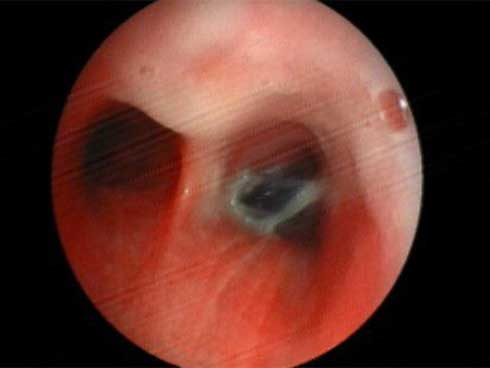

Tiếp tục tiến hành nội soi phế quản bằng ống nội soi mềm thì phát hiện dị vật có màu đen, dạng elip, kích thước khoảng 2cm, trông giống hạt sapôchê. Ngay sau đó, các bác sĩ đã tiến hành gắp dị vật ra. Sau 1 ngày, sức khỏe bệnh nhân đã hoàn toàn ổn định.